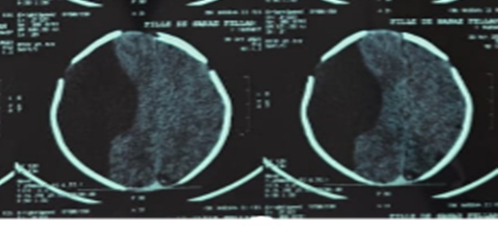

Cranial ultrasound, CT (Figure 1), and MRI (Figure 2) demonstrated a large right fronto-temporo-parietal extra-axial cystic lesion with significant mass effect and midline shift. Laboratory results were normal.

Figure 1: Non-contrast axial CT scan demonstrating a large right fronto -temporo-parietal extra-axial hypodense collection, exerting significant mass effect on the midline structures.